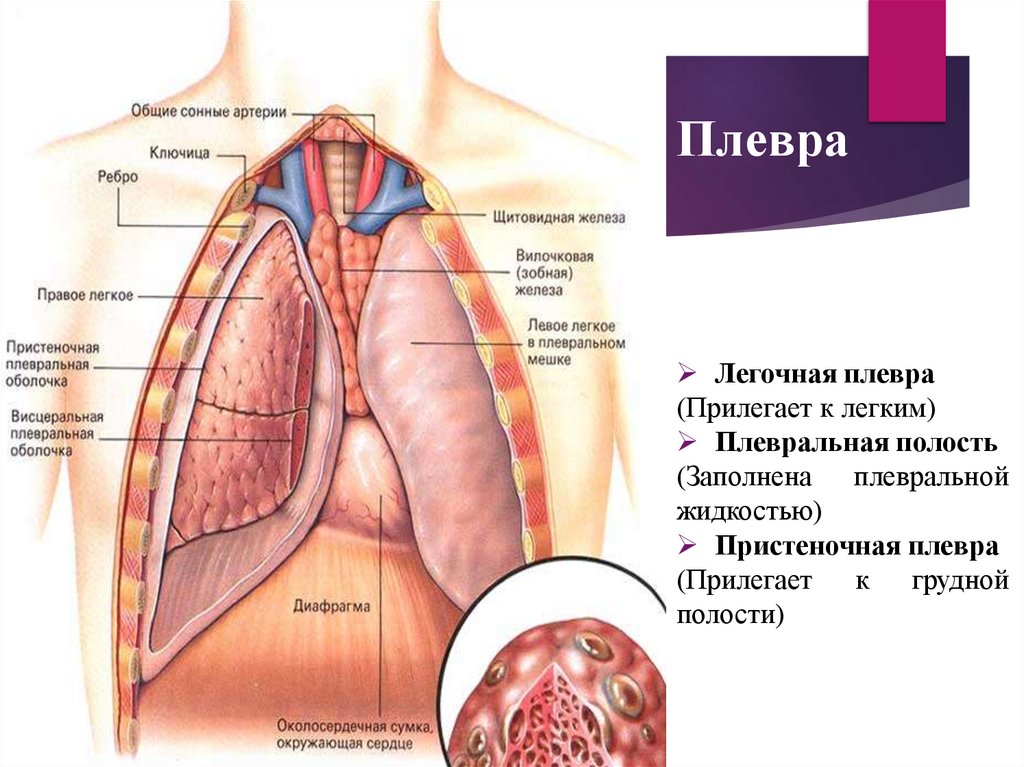

Дифференциальная диагностика заболеваний плевры